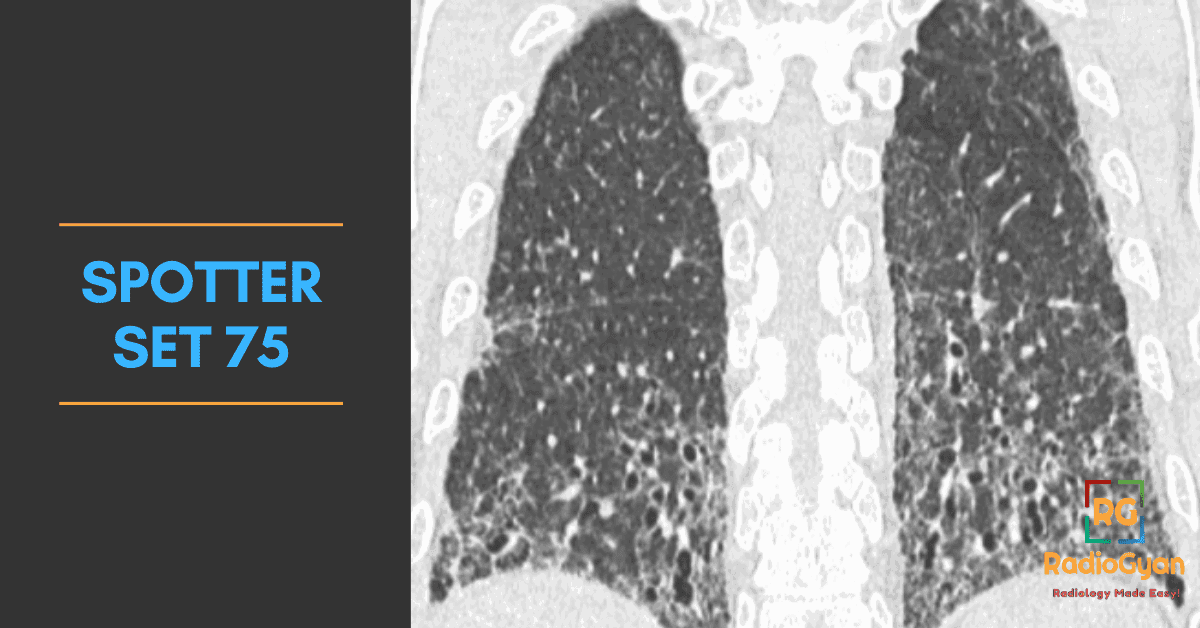

Explore high-yield radiology spotters with detailed explanations and case discussions to enhance your diagnostic skills at RadioGyan.com.